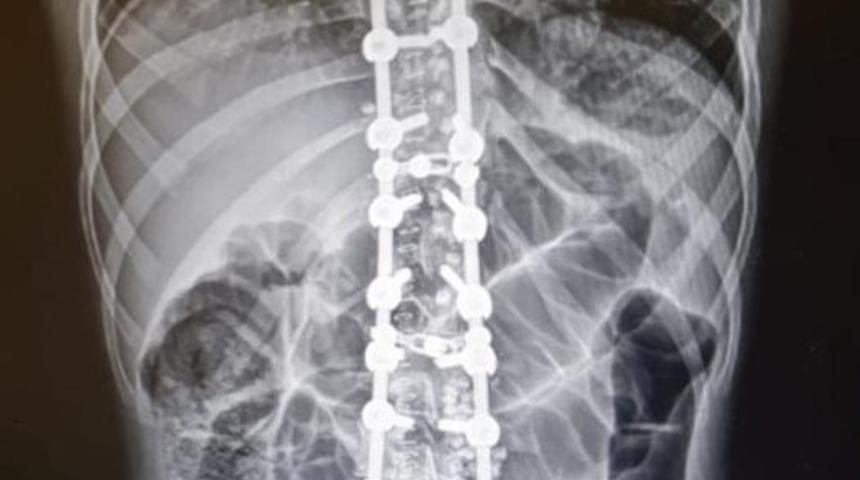

Ordu’nun Fatsa ilçesinde 17 yaşındaki B.Ç., yaklaşık 10 yıldır omurgasındaki eğilmeden şikayeti nedeniyle Fatsa Devlet Hastanesine başvurdu. Gerekli tetkikleri yapılan hasta, Ortopedi ve Travmatoloji Uzmanı Opr. Dr. Mehmet Onur Sarıhan tarafından ameliyat edildi. Sağlığına kavuşan hasta taburcu edildi.

Skolyoz rahatsızlığı ve yapılan ameliyatla ilgili bilgi veren Opr. Dr. Mehmet Onur Sarıhan, “Skolyoz omurganın yana 10 derecenin üzerindeki eğilmedir. Normal ve sağlıklı omurgada, omurlar arkadan bakıldığında yukarıdan aşağıya yani boyun, sırt ve bel bölgelerinde düz bir hat şeklinde uzanır. Skolyoz da ise omurlar sağa veya sola doğru yer değiştirir ve aynı zamanda kendi eksenleri etrafında döner. Bu nedenle üç boyutlu bir deformite (şekil bozukluğu) olarak tanımlanır. Skolyoza bağlı olarak omurga dışında kalça, göğüs kafesi ve kürek kemiklerinde de kaymalar oluşur, duruş ve görüntü bozukluğu ortaya çıkar. Gelişme çağındaki çocuklarda bu durum, gelişen ve büyüyen omurgada anormal yüklenmeye ve bunun sonucu olarak da omurlarda deformelere neden olur” dedi.

Skolyoz (omurga eğriliği) ve omurgada dar kanal cerrahisi ameliyatlarının Fatsa’da başarılı bir şekilde yapıldığını söyleyen Opr. Dr. Mehmet Onur Sarıhan, “Genç yaşlarda tespit edildiğinde tedavide başarı oranı ciddi olarak artmaktadır. Bu tür rahatsızlığı olanlar artık ilçemizde başarılı bir şekilde tedavilerini olabilecekler” diye konuştu.